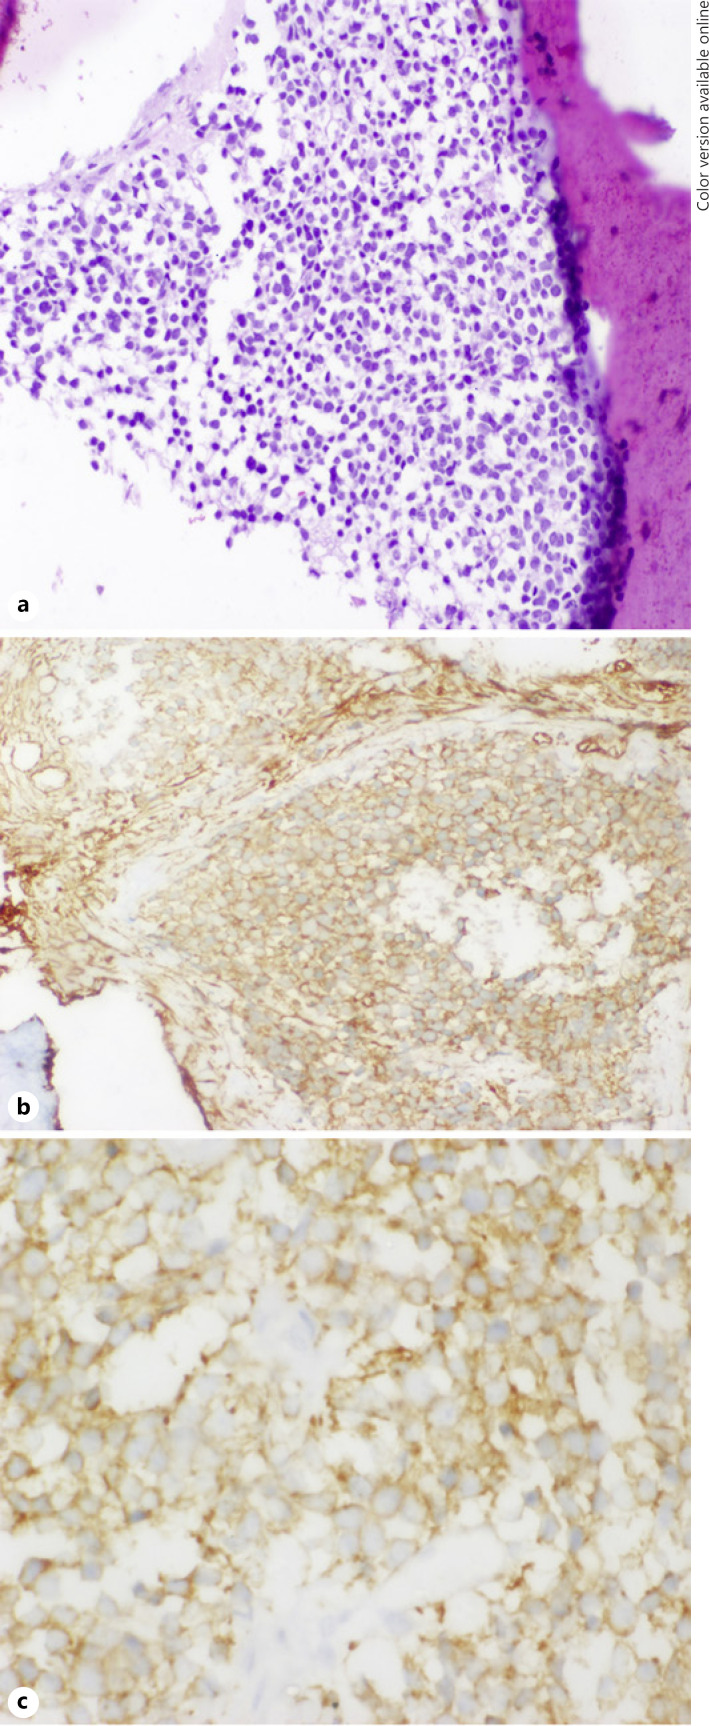

Six and a half years after treatment, the child presented with pain in his left proximal forearm. On examination, there was mild tenderness over the proximal ulnar bone, with no obvious swelling or redness. Radiograph showed lytic sclerotic lesion involving proximal meta-diaphysis of the left ulna with wide zone of transition, solid periosteal reaction, and cortical irregularities (shown in Fig. 1). MRI further confirmed the lesion limited to proximal meta-diaphysis of the left ulna seen as abnormal STIR hyperintensity involving the marrow with cortical erosion and associated soft tissue component (shown in Fig. 2). The bone scan showed uptake only at the left upper forearm. Bone marrow and CSF analysis did not show any evidence of disease. The CT thorax did not show any pulmonary metastasis. Bone biopsy was done, and histopathology showed infiltration of the intertrabecular space by sheets of small round cells having scanty cytoplasm and hyperchromatic nuclei. The differentials considered were small cell osteosarcoma, Ewing's sarcoma, and metastatic small round cell neoplasm. Radiology was not suggestive of osteogenic sarcoma; hence, small-cell osteosarcoma was ruled out. Immunohistochemistry showed tumour cells to be chromogranin cytoplasmic granular positive, synaptophysin diffuse strong positive, CD56 diffuse strong positive, MIC2 cytoplasmic and membrane positive, desmin and myogenin negative (shown in Fig. 3). The tumour cells were positive for synaptophysin, chromogranin, and CD 56, which denotes neuroendocrine/neuroectodermal differentiation. Retinal markers were not done due to non-availability. Ewing's sarcoma translocations done were negative for EWS-FLI1 type 1 and type 2 and EWS-ERG, which together account for 95% of translocations associated with Ewing's sarcoma. Tumour cells in Ewing's sarcoma can be CD56 and synaptophysin positive, but chromogranin negative. Positivity for chromogranin, absence of typical crisp membrane pattern of staining for CD99, and negative translocation ruled out Ewing's sarcoma. Hence, we considered metastatic small round-cell neoplasm in this case. Based on the immunoprofile which showed positive staining for chromogranin, synaptophysin, and CD56, negative RT-PCR for translocations of Ewing's sarcoma, and a positive history of bilateral RB, the possibility of metastatic RB was highly favoured [13].

Fig. 3.

HE stain ×100: sheets of small round cells with scanty cytoplasm and hyperchromatic nuclei (a); MIC2 ×400 showing cytoplasm and membrane positivity (b); synaptophysin ×400 showing diffuse strong membrane positivity (c).